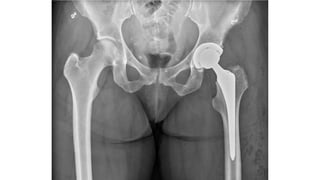

This document discusses femoral fractures, categorized by their location and severity, with classifications such as Garden classification. It outlines the types of fractures, including valgus impacted, non-displaced, partially displaced, and fully displaced, along with their surgical treatment options. Additionally, it briefly describes distal femur fractures, which occur just above the knee joint.